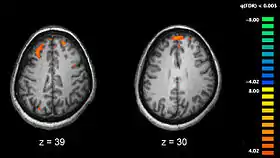

Phonological processing yields phonological codes (or representations) which are then used in speech processing to reach higher-level lexicon representations that are essential for auditory speech comprehension [6]. Strong empirical evidence shows the involvement of the posterior middle temporal lobe regions in accessing lexical and semantic information [6][8][11]. Lesion studies of the posterior temporal lobe have also supported this evidence. Elizabeth Bates and her colleagues studied 101 left-hemisphere aphasic patients and found that lesions to the middle temporal gyrus (MTG) most accurately predicted auditory comprehension deficits, with a significant deficit also observed with dorsolateral prefrontal cortical lesions. Whereas, lesions to the insula and arcuate/superior longitudinal fasciculus affected verbal fluency the most [12]. Functional magnetic resonance imaging studies (see Figure 3 for an example of an fMRI scan) have further implicated the posterior middle temporal lobe regions in semantic processing. In a semantic decision task in research conducted by Jeffrey Binder and colleagues, activations were found in both sides of the STS and almost all of the MTG in the left hemisphere. They also found that this activation spread ventrally across the inferior temporal gyrus (ITG). The authors found further activations in the angular gyrus, anterior and posterior cingulated gyrus, portions of the precuneus, retrosplenial cortex, and cinglulate isthmus in the left hemisphere; as well as subcortical activations in the anterior thalamus in the left hemisphere. [11]. Many positron emission tomography (PET) studies (see Figure 4 for an example of a PET scan) examined the activated areas in response to semantic processing. They too found left lateralized non-STG temporparietal regions; including the MTG, inferior temporal gyrus (ITG), and the angular gyrus [13] [14][15].